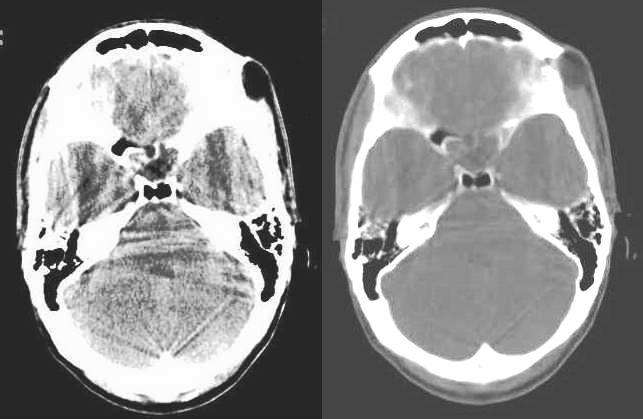

以下是引用随光逐影在2009-6-13 7:45:00的发言:[br]考虑皮样囊肿或表皮样囊肿。